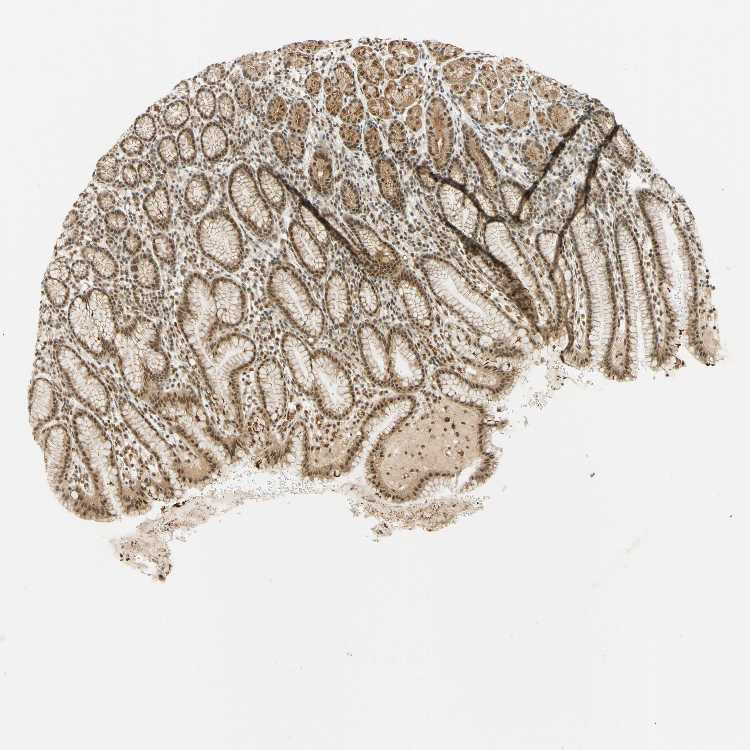

TISSUE PRIMARY DATA STOMACH Show tissue menu

STOMACH 1 - Antibody stainingi

Antibody staining in the annotated cell types in the current human tissue is reported as not detected, low, medium, or high, based on conventional immunohistochemistry profiling in selected tissues. This score is based on the combination of the staining intensity and fraction of stained cells.

Each image is clickable and will lead to virtual microscopy that enables deeper exploration of all samples and also displays staining intensity scores, fraction scores and subcellular localization as well as patient and tissue information for each sample.

Antibody HPA018248Antibody HPA019127Antibody CAB009196

Glandular cells HighHighMedium